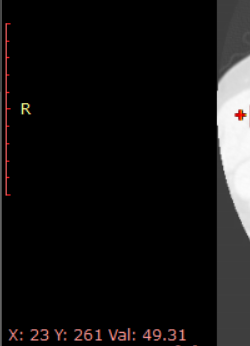

本篇文章实现radiant获取某一点的像素值。

dicom图像原点为图像左上点,x轴正方向为行方向,y轴正方向为列方向。

因此随着鼠标移动,可以显示某一点的坐标点。

获取CT图像的CT值